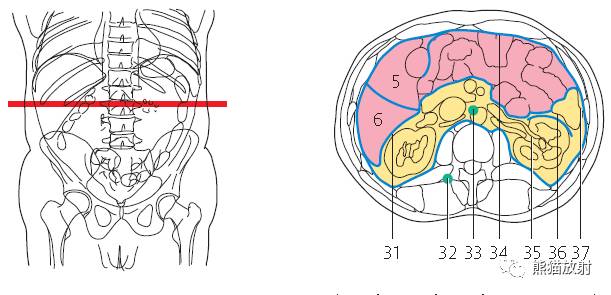

第八层

1、肝脏;2、右肾动脉;3、胆囊;4、结肠右曲;5、十二指肠;6、下腔静脉;7、肠系膜上动脉及静脉;8、腹主动脉;9、左肾静脉;10、横结肠;11、腹直肌;12、空肠;13、降结肠;14、内斜肌;15、外斜肌;16、右肾;17、肾锥体;18、腰方肌;19、肾皮质;20、腰大肌;21、膈肌;22、胸椎;23、椎管;24、棘肌;25、腰动脉及静脉;26、最长肌;27、左肾动脉;28、髂肋肌;29、肾盂;30、背阔肌;31、肝肾隐窝;32、肋间淋巴结;33、腰淋巴结;34、大网膜;35、肾门;36、左侧肠系膜结肠沟;37、左结肠旁沟。